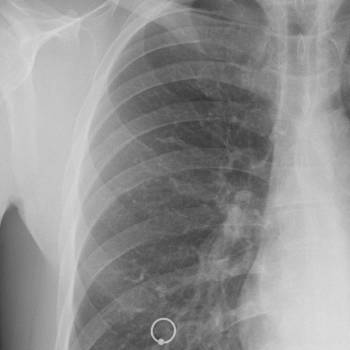

갑자기 살이 빠지는 이유 6. 결핵

결핵은 체중 감소를 유발할 수 있는 전염성 질환입니다. 결핵 환자들은 종종 식욕 부진과 함께 지속적인 기침, 피로, 발열, 야간 발한 등의 증상을 경험합니다. 결핵균이 신체의 에너지를 과도하게 소모하여 체중 감소를 초래합니다. 결핵은 특히 폐를 침범하지만, 신체의 다른 부위에도 영향을 미칠 수 있습니다.